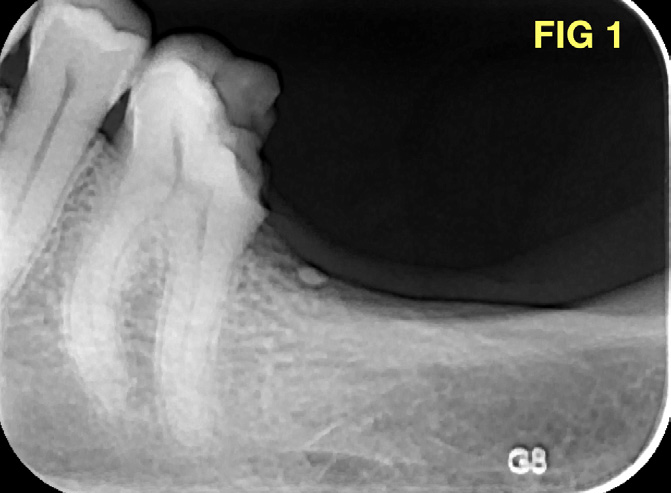

A 42 year old female patient came to the office complaining about crown fracture and severe pain in the left mandibular posterior area. Intraoral and radiographic examination revealed disto-occlusal decay in tooth 3.6 (fig1), and exposure of the distal pulp horn. Tooth was highly sensitive to thermal cold test; an acute pulpitis was diagnosed and an endodontic orthograde treatment was proposed and accepted. Following a minimally invasive approach, access cavity was designed starting from the distal portion of the tooth, to avoid unnecessary loss of dentinal structure…